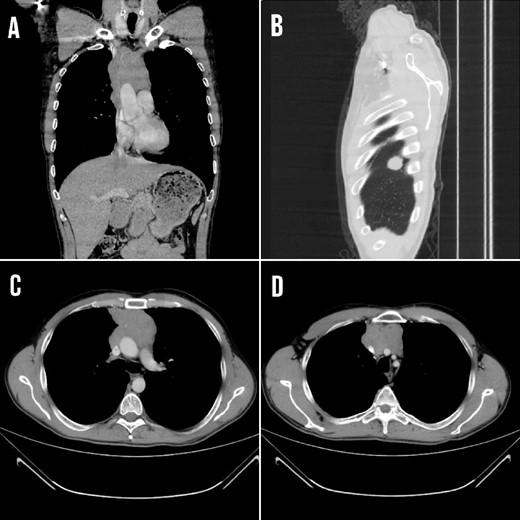

The symptoms persisted and aggravated with dysphagia, weight loss, dyspnea on exertion, and facial and upper limb edema due to compression of the SVC. Laboratory test results are demonstrated in Table 1. A CT scan showed that the mass compresses and invades the major neck veins and the SVC with a thrombus inside, with the presence of a right diaphragmatic metastasis (Fig. 1).

(A) CT coronal section showing the mediastinal lesion. (B) Right diaphragm metastasis at the posterior costal margin at the level of 4 and 5 thoracic ribs (C and D) Transverse section demonstrating the mass that compressed and invaded the major neck veins and the SVC.